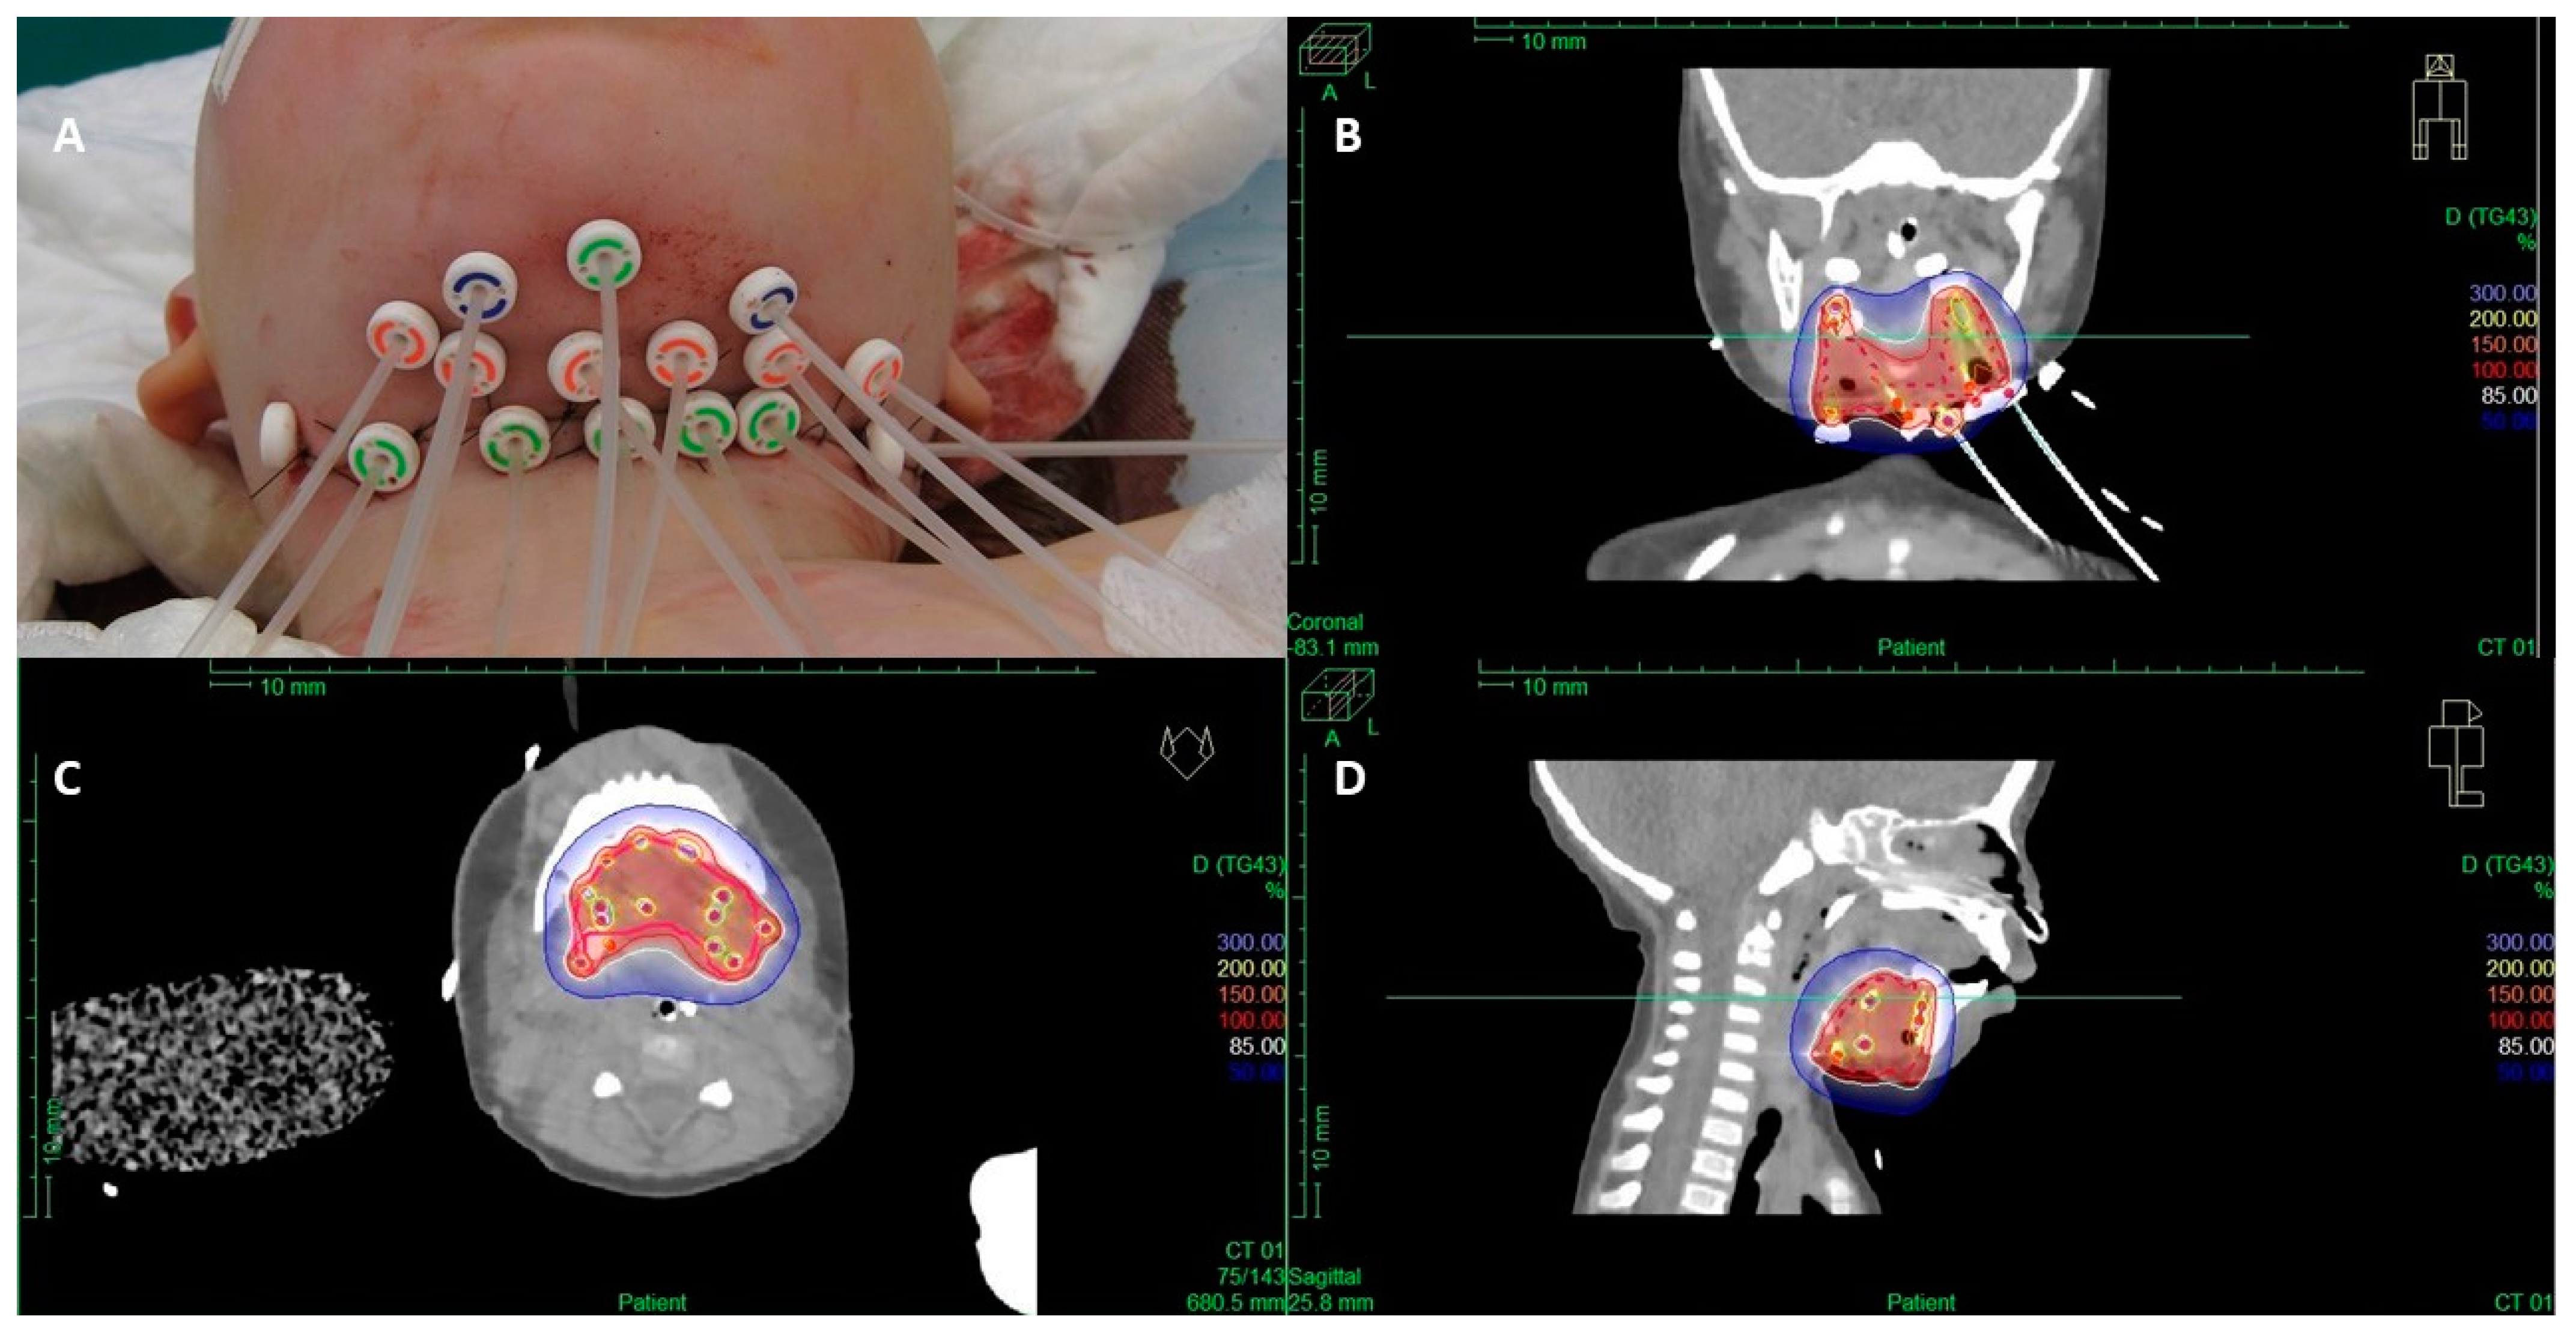

3.3. Brachytherapy

- Gaze, M.N.; Smeulders, N.; Ackwerh, R.; Allen, C.; Bal, N.; Boutros, M.; Cho, A.; Eminowicz, G.; Gill, E.; Fittall, M.W.; et al. A national referral service for paediatric brachytherapy: An evolving practice and outcomes over thirteen years. Clin. Oncol. 2023, 35, 237–244. [Google Scholar] [CrossRef] [PubMed]

- Blank, L.E.; Koedooder, K.; Pieters, B.R.; van der Grient, H.N.; van de Kar, M.; Buwalda, J.; Balm, A.J.; Merks, J.H.; Strackee, S.D.; Freling, N.J.; et al. The AMORE protocol for advanced-stage and recurrent non-orbital rhabdomyosarcoma in the head-and-neck region of children: A radiation oncology view. Int. J. Radiat. Oncol. Biol. Phys. 2009, 74, 1555–1562. [Google Scholar] [CrossRef]

- Fajardo, R.D.; Scarzello, G.; Gaze, M.N.; Boterberg, T.; Cameron, A.; Fuchs, J.; Guérin, F.; Hoskin, P.; Krasin, M.J.; Kroon, P.; et al. Brachytherapy for rhabdomyosarcoma: Survey of international clinical practice and development of guidelines. Radiother. Oncol. 2024, 195, 110273. [Google Scholar] [CrossRef]